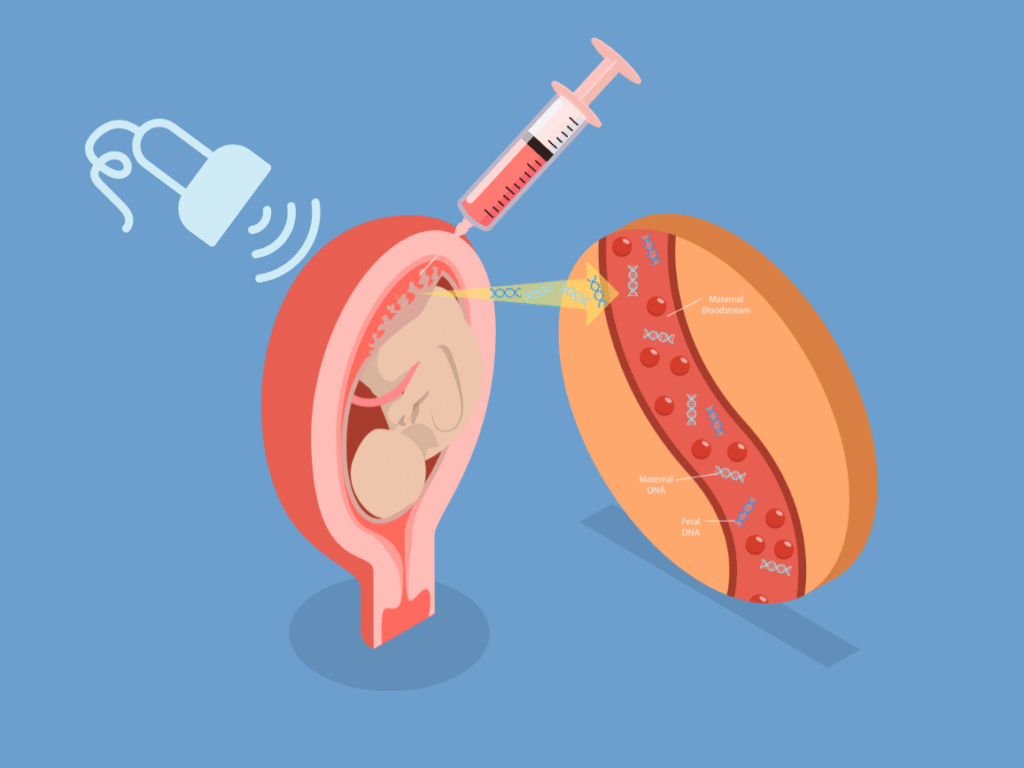

1. Amniocentesis

Amniocentesis involves collecting a small sample of amniotic fluid that surrounds the baby in the womb. It helps detect chromosomal and genetic conditions, such as Down syndrome and neural tube defects, with high accuracy. The procedure is performed under continuous ultrasound guidance to ensure safety.

2. Chorionic Villus Sampling (CVS)

CVS is an early genetic test done between 10–13 weeks of pregnancy. A tiny sample of placental tissue (chorionic villi) is taken to analyze the baby’s chromosomes. CVS provides early answers for families at risk of genetic disorders or who have had abnormal screening results.

3. Fetal Blood Sampling

Also known as cordocentesis, this test involves drawing a small sample of fetal blood from the umbilical cord to check for fetal anemia, infections, or chromosomal abnormalities. It is typically performed when earlier tests are inconclusive or when a more detailed genetic or hematologic study is needed.